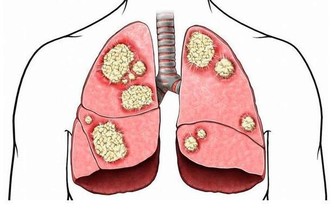

*****2.保護心臟*****

一項希臘研究顯示,每周至少3次,每次午睡30分鐘,可使因心髒病猝死的風險降低37%;另有資料證明,在有午休習慣的國家和地區,冠心病的發病率要比不午睡的國家低得多。

研究人員認為,這可能得益於午休能舒緩心血管系統,並降低人體緊張度。